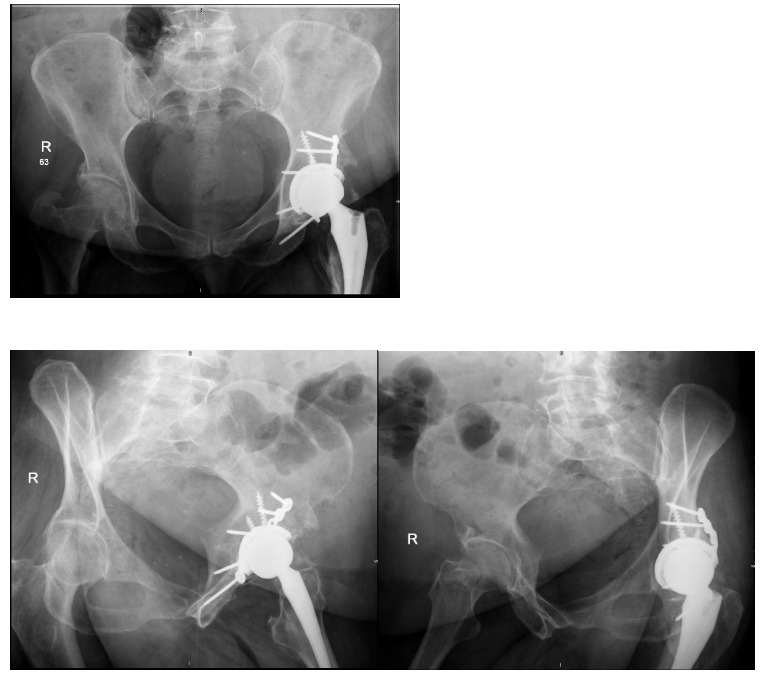

A 64-year-old female with diabetes, hypertension, and dyslipidemia was involved in a motor vehicle accident, resulting in significant injuries. She presented to the Emergency Department via Medivac and underwent a comprehensive trauma assessment. Orthopedic evaluations reveal a fractures dislocation of the left acetabulum with a posterior wall fracture and a femoral head fracture (Figure 1. Figure 2, Figure 3). Additionally, a minimally displaced fractures of the left tibial plafond was identified. Due to the complexity of her injuries and considering her age, a surgical plan was formulated for fixations of the acetabular and femoral head fractures, along with total hip replacements on the left side, and fixations of the tibial plafond fractures. After induction of general anesthesia and regional block, the patient was positioned in lateral decubitus for the hip procedures. Utilizing the Kocher-Langenbeck approach, the posterior wall fracture was stabilized with lag screws and a buttress plate (Figure 4A, 4B). The hip was then dislocated, the femoral neck cut, and the acetabulum reamed. A Stryker Trident cup size 46 was inserted for a press-fit, augmented with three screws, and a metal liner for dual mobility was added. Subsequently, the femur was broached, and an Accolade stem size 2 with a double head was implanted, ensuring excellent stability and appropriate legs length (Figure 4C). The operation concluded with thorough irrigation and closure in layers. The patient was then repositioned supine to address the tibial plafond fracture, which was stabilized with a single medial plate, followed by application of a dry dressing and a below-knee backslabs. Postoperatively, the patient experienced mild pain but was otherwise stable. Dressings on the left hip and ankle were intact, with ankle motion preserved and a palpable dorsalis pedis pulse. She began mobilization with physiotherapy from day one and showed no active complaints throughout her recovery, proceeding smoothly until discharge (Figure 5).